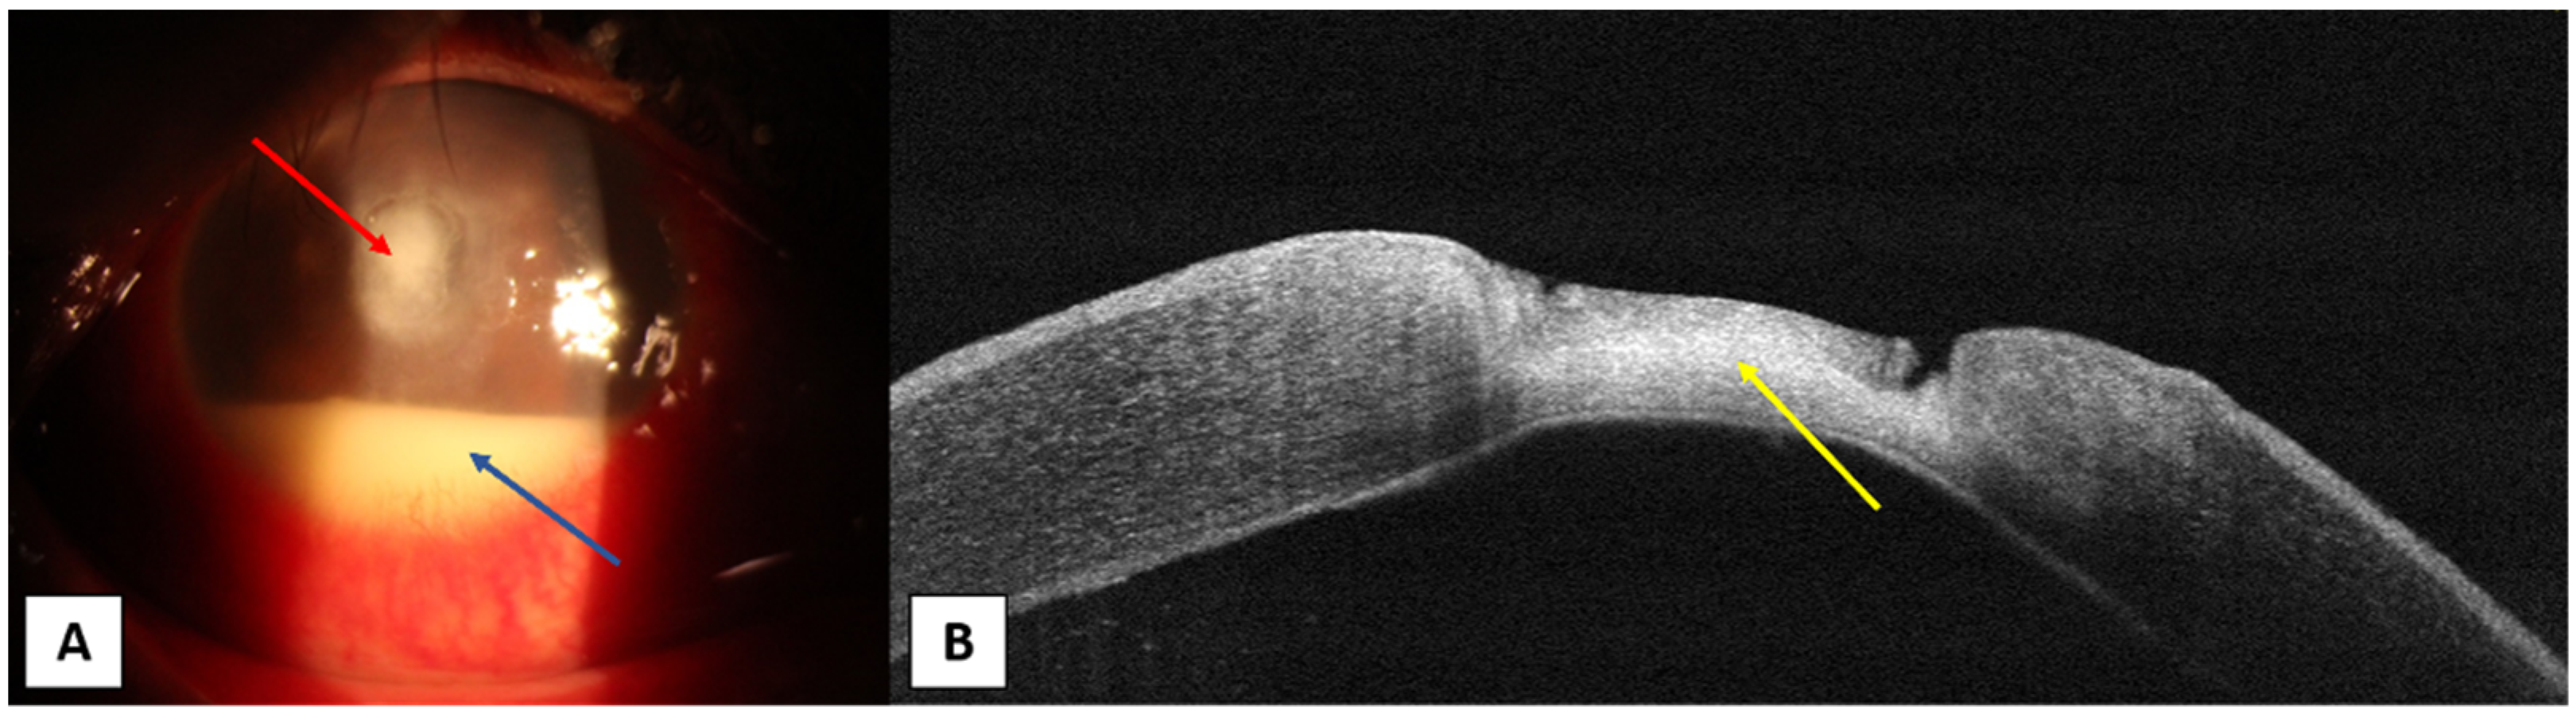

- Takezawa, Y.; Suzuki, T.; Shiraishi, A. Observation of Retrocorneal Plaques in Patients with Infectious Keratitis Using Anterior Segment Optical Coherence Tomography. Cornea 2017, 36, 1237–1242. [Google Scholar] [CrossRef] [PubMed]

- Abbouda, A.; Estrada, A.V.; Rodriguez, A.E.; Alio, J.L. Anterior segment optical coherence tomography in evaluation of severe fungal keratitis infections treated by corneal crosslinking. Eur. J. Ophthalmol. 2014, 24, 320–324. [Google Scholar] [CrossRef] [PubMed]